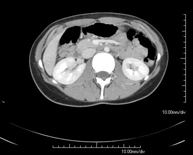

Diagnostic test that involves obtaining high-definition anatomical images of the abdomen (liver, gallbladder, bile duct, pancreas, spleen, stomach, intestines, kidneys, vascular structures, bladder, uterus and ovaries, etc.) using CT (computed tomography) equipment. These images are then studied at a workstation capable of producing two-dimensional reconstructions in different spatial planes, and also 3D (volumetric) reconstructions. Most studies require the use of iodinated contrast to improve image definition.